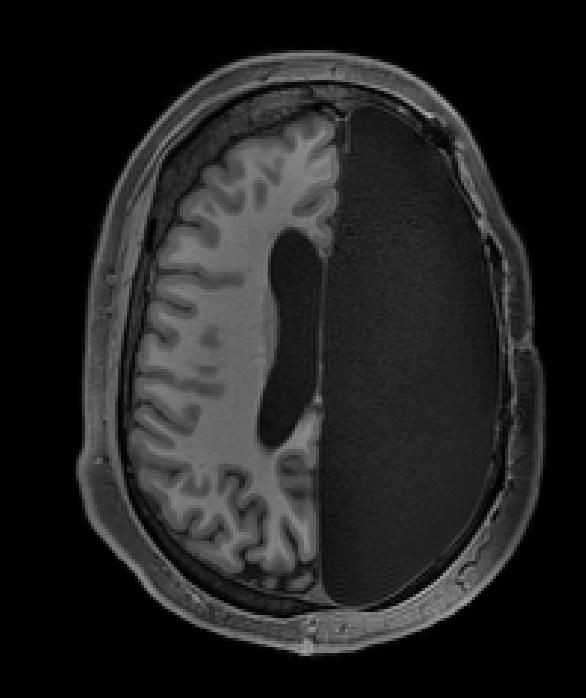

消失的一半大脑

对于大脑半球被切除的患者,其不同大脑网络之间的连接性更强

大脑具有非凡的改变和适应能力,比如少数人在孩童时期为了减少癫痫发作而切除了一半大脑之后,还能够维持正常的功能。根据一项新的研究,尽管这些人的大脑少了整整一半,但仍然运转良好,因为剩下的一半得到了强化。有6名20多岁和30多岁的成年人参与了这项研究,他们在3个月到11岁之间时切除了一半大脑。研究人员分析了他们的大脑活动,并与大脑完好的人进行了比较。

脑部扫描显示,这些只有一个大脑半球的参与者,其大脑中涉及同一网络(如视觉)的区域,具有与大脑完好的人相同的协同效果。他们还发现,对于大脑半球被切除的患者,其不同大脑网络之间的连接性更强,这表明大脑能够弥补自身很大一部分的缺失。